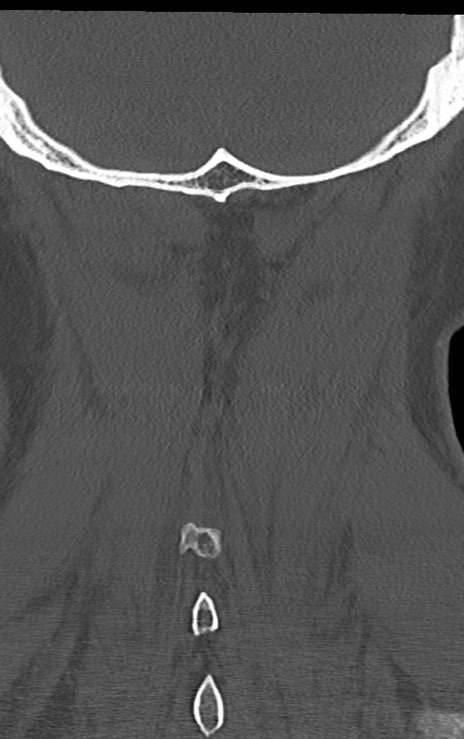

【整形】TIPS症例7 頚椎CT(冠状断像)

【症例】60歳代男性

【主訴】両手のしびれ

【現病歴】15年前より右手のしびれあり。4ヶ月前から左手のしびれあり。最近、症状増悪あり。

頚椎CT